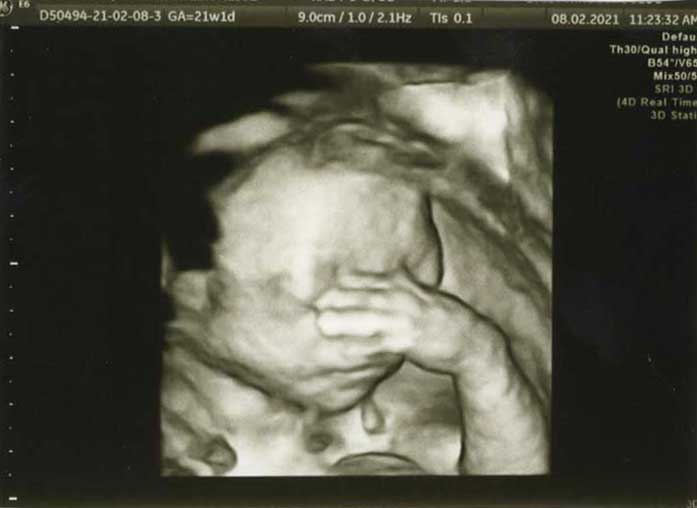

3D/4D HD LIVE

Στο ιατρείο μας προσφέρουμε υψηλής ευκρίνειας 3D και 4D τεχνολογία απεικόνισης του εμβρύου. Η τεχνολογία αυτή αποτελεί ένα ακόμα σημαντικό διαγνωστικό όπλο στη φαρέτρα του προγεννητικού ελέγχου, ενώ ταυτόχρονα ενισχύει την ανάπτυξη του δεσμού ανάμεσα στους μελλοντικούς γονείς και το μωρό τους.